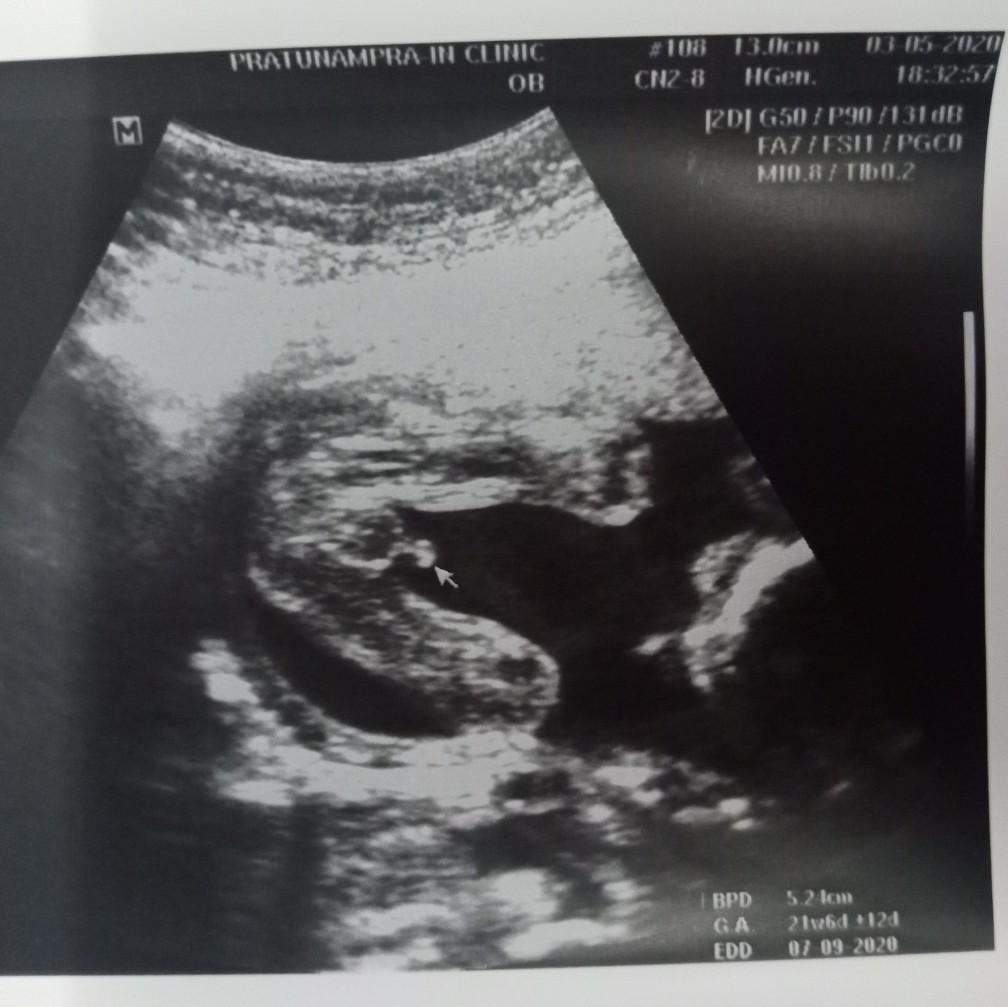

ซาวด์ตอน19+3 ค่ะ